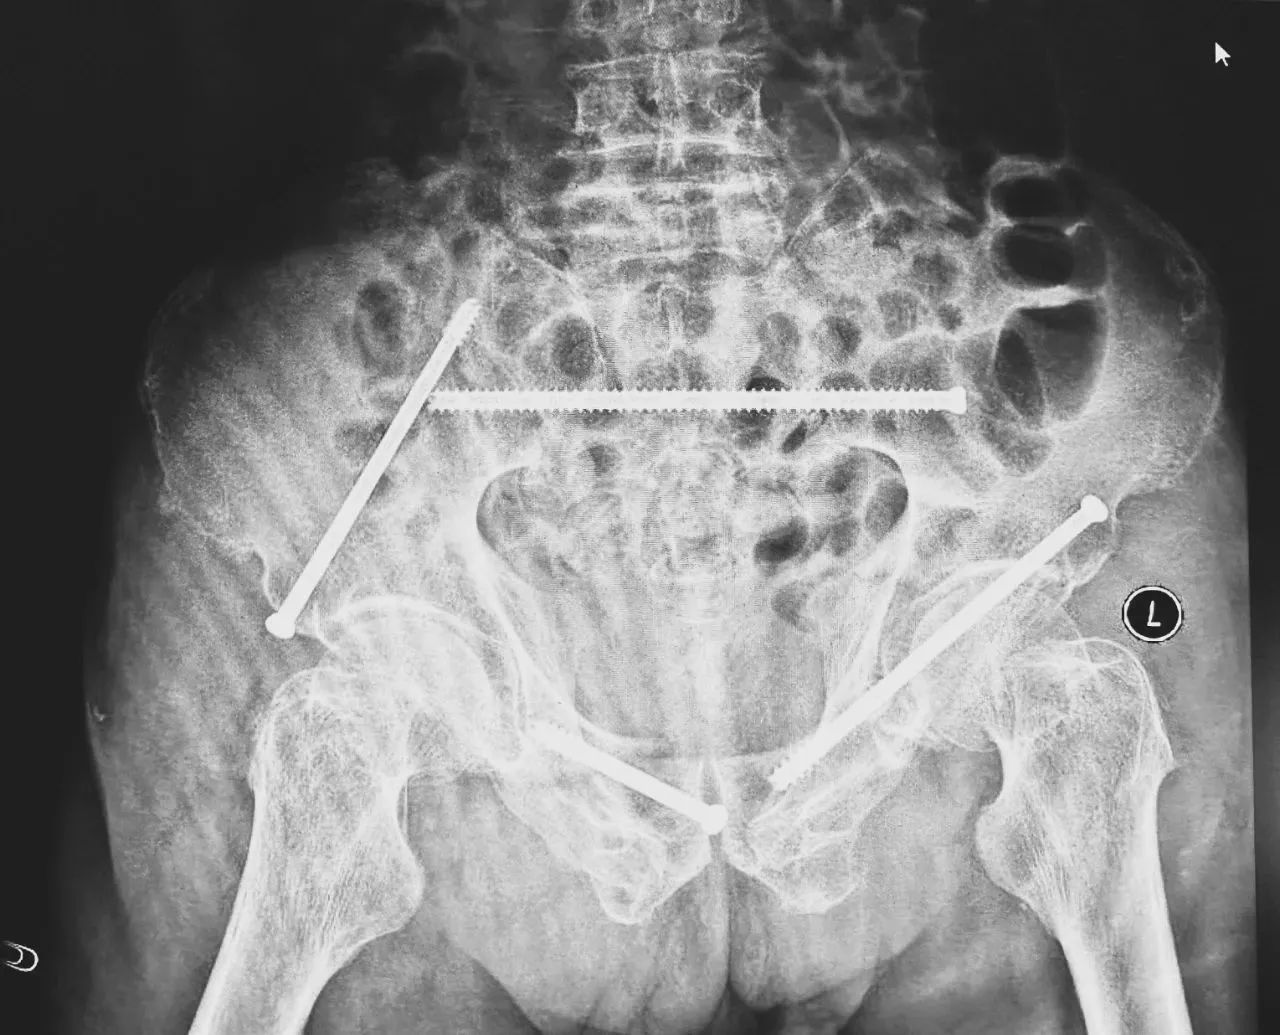

無(wú)影燈下,智能骨科團(tuán)隊(duì)將患者示蹤器,放在左側(cè)髂前上棘,使用術(shù)中三維影像設(shè)備獲取骨盆的三維圖像,掃描結(jié)果傳輸至機(jī)器人導(dǎo)航系統(tǒng),完成螺釘置入的位置和走形,并在機(jī)器人的引導(dǎo)下分別置入4枚通道螺釘。置入后再次進(jìn)行CT掃描驗(yàn)證,證實(shí)導(dǎo)針精確置入。

在骨科手術(shù)機(jī)器人毫米級(jí)精度的引導(dǎo)下,這項(xiàng)原本高難度、高風(fēng)險(xiǎn)的手術(shù)變得更加精準(zhǔn)高效。手術(shù)共計(jì)耗時(shí)1個(gè)半小時(shí),術(shù)中出血不到20毫升,每枚螺釘置入位置的切口長(zhǎng)度約1.5厘米,完美達(dá)到了預(yù)期。術(shù)后,王大爺安全返回病房。

術(shù)后第二天,醫(yī)生團(tuán)隊(duì)復(fù)查X片顯示螺釘植入位置非常滿意,骨折基本達(dá)到穩(wěn)定復(fù)位,同時(shí),復(fù)查的全血細(xì)胞計(jì)數(shù)中,血紅蛋白指數(shù)為102g/L。術(shù)后第三天,在智能骨科病房護(hù)理團(tuán)隊(duì)及康復(fù)師的指導(dǎo)和護(hù)理下,王大爺可以坐立在床上。術(shù)后第四天,王大爺迎來(lái)了出院日,“得虧有了這么先進(jìn)的醫(yī)療技術(shù),讓我還能下地行走,謝謝你們!”

螺釘植入位置非常滿意